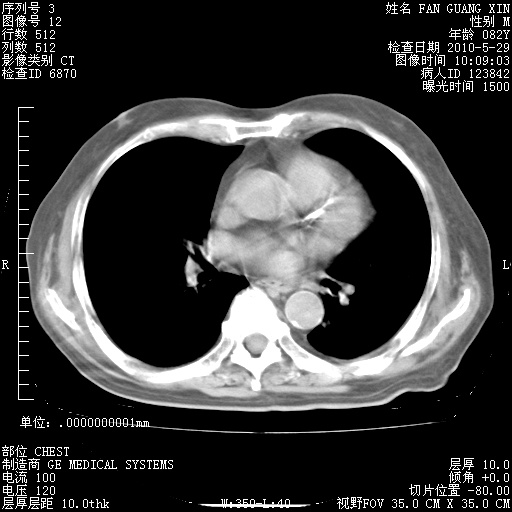

治疗3周后的肺部CT纵隔窗

再治疗10天后的肺部CT

再治疗10天后的肺部CT 纵膈窗